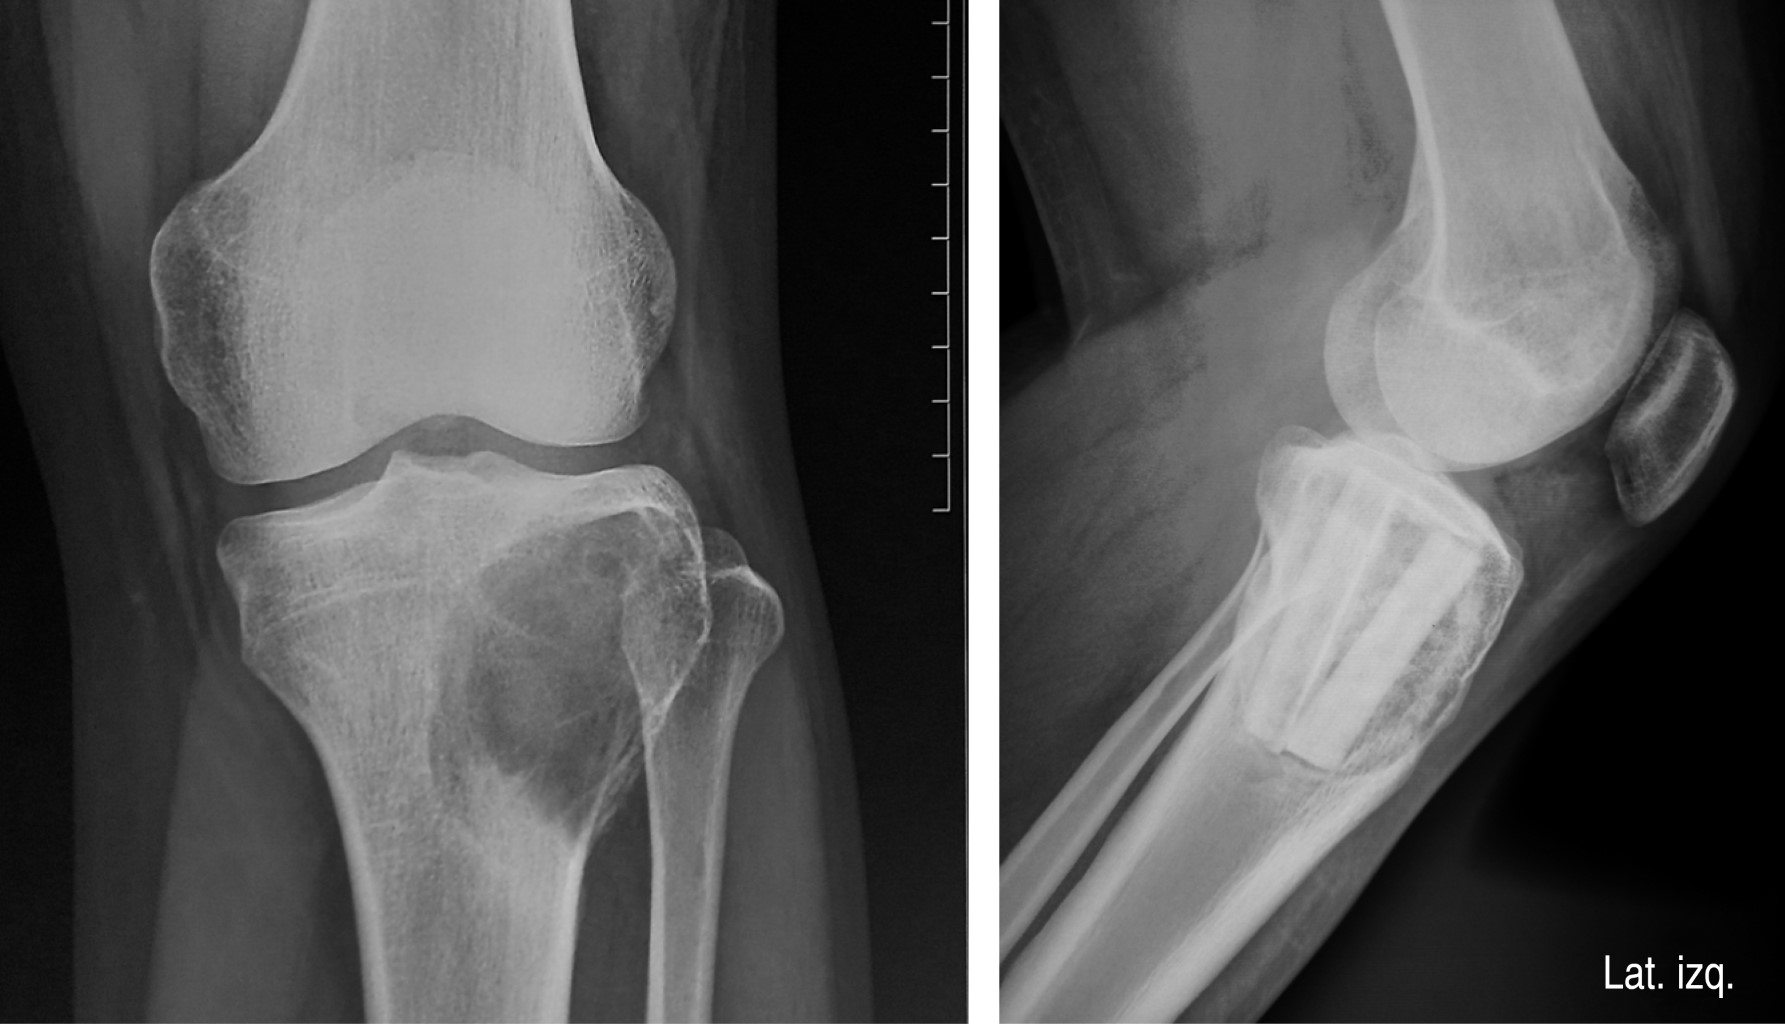

Caso 2. Paciente masculino de 20 años que, a consecuencia de gonalgia progresiva izquierda, fue llevado a estudios de radiología convencional. En este estudio se observó una lesión osteolítica en la meta-epífisis proximal de la tibia, involucrando el platillo tibial lateral. Por tomografía y resonancia magnética se identificó integridad cortical. La biopsia diagnosticó quiste óseo aneurismático, razón por la que se sugirió y realizó una resección intralesional con soporte estructural a base de aloinjertos diafisarios de peroné y se complementó con aloinjerto en chips cortico-esponjosos. El producto de la resección intralesional fue analizado y el diagnóstico fue modificado al de tumor óseo de células gigantes. Esta neoplasia es definida como un tumor óseo localmente agresivo que raramente metastatiza, compuesto de células neoplásicas estromales mononucleadas de apariencia monótona, mezcladas con macrófagos y células gigantes que semejan osteoclastos.10 Pese al cambio en el diagnóstico, se decidió vigilar la evolución. El aloinjerto progresivamente logró consolidar la lesión y el soporte de carga se permitió iniciar a los tres meses del evento quirúrgico completándose a los cinco. Nunca se restringió la movilidad de la rodilla (Figura 2).

Figura 2